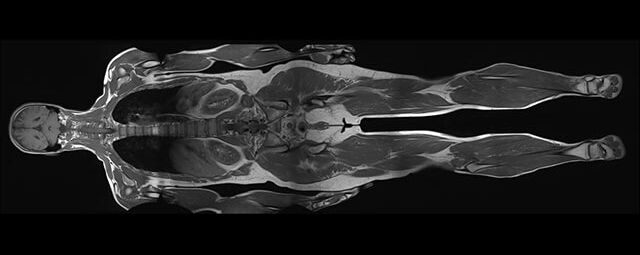

Im Magnetresonanztomographen liegt die zu untersuchende Person in einem starken, homogenen Magnetfeld. Dieses Magnetfeld bewirkt eine gemeinsame Ausrichtung der Wasserstoffprotonen im Körper entlang der Längsachse des Magnetfeldes. Wird nun diesen Teilchen Energie in Form von Radiowellen in einer genau abgegrenzten Frequenz zugeführt, so werden sie aus ihrer ursprünglichen Orientierung abgelenkt.

Die zugeführte Energie wird in gewebespezifischer Weise wieder abgegeben. Ein hochempfindliches Computersystem misst die unterschiedliche Energieabgabe und setzt sie in Bildinformationen um. Jede Körperregion kann somit durch Schnittbilder in allen Raumebenen oder durch dreidimensionale Rekonstruktionen mit einem exzellenten Weichteilkontrast dargestellt werden. Es besteht keine Belastung durch Röntgenstrahlen.

Die MRT wird immer dann eingesetzt, wenn Verfahren mit Röntgen oder Ultraschall keine klaren Aussagen liefern können oder wenn dynamische Prozesse des Körpers untersucht werden sollen.